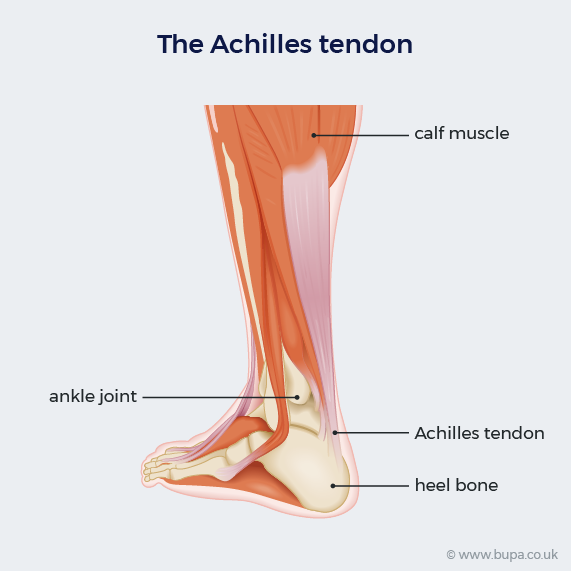

Achilles tendinitis Information Mount Sinai New York

Causes of Achilles Tendon Pain Advanced Foot Ankle Care

Achilles Tendinopathy Symptoms Causes and Treatment Bupa UK

Achilles tendonitis pain causes symptoms and exercises

Achilles tendon pain Causes. when to see a doctor and treatment